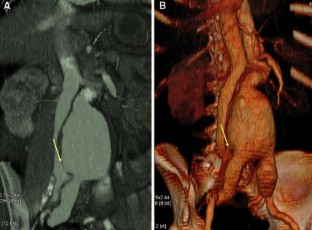

Fig. 3. A, B.